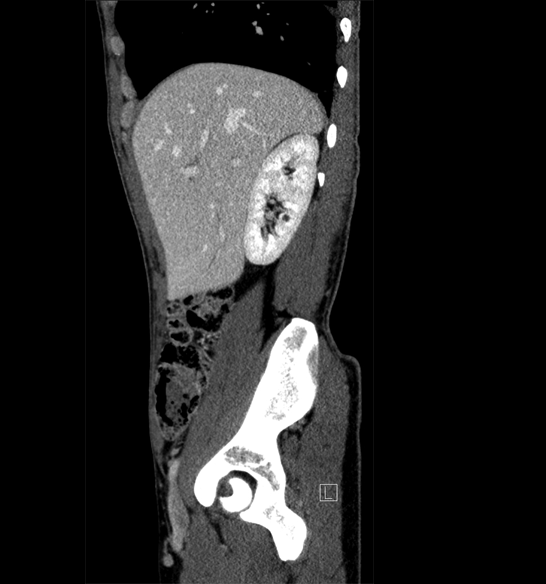

Body

Covers abdominal CT anatomy.